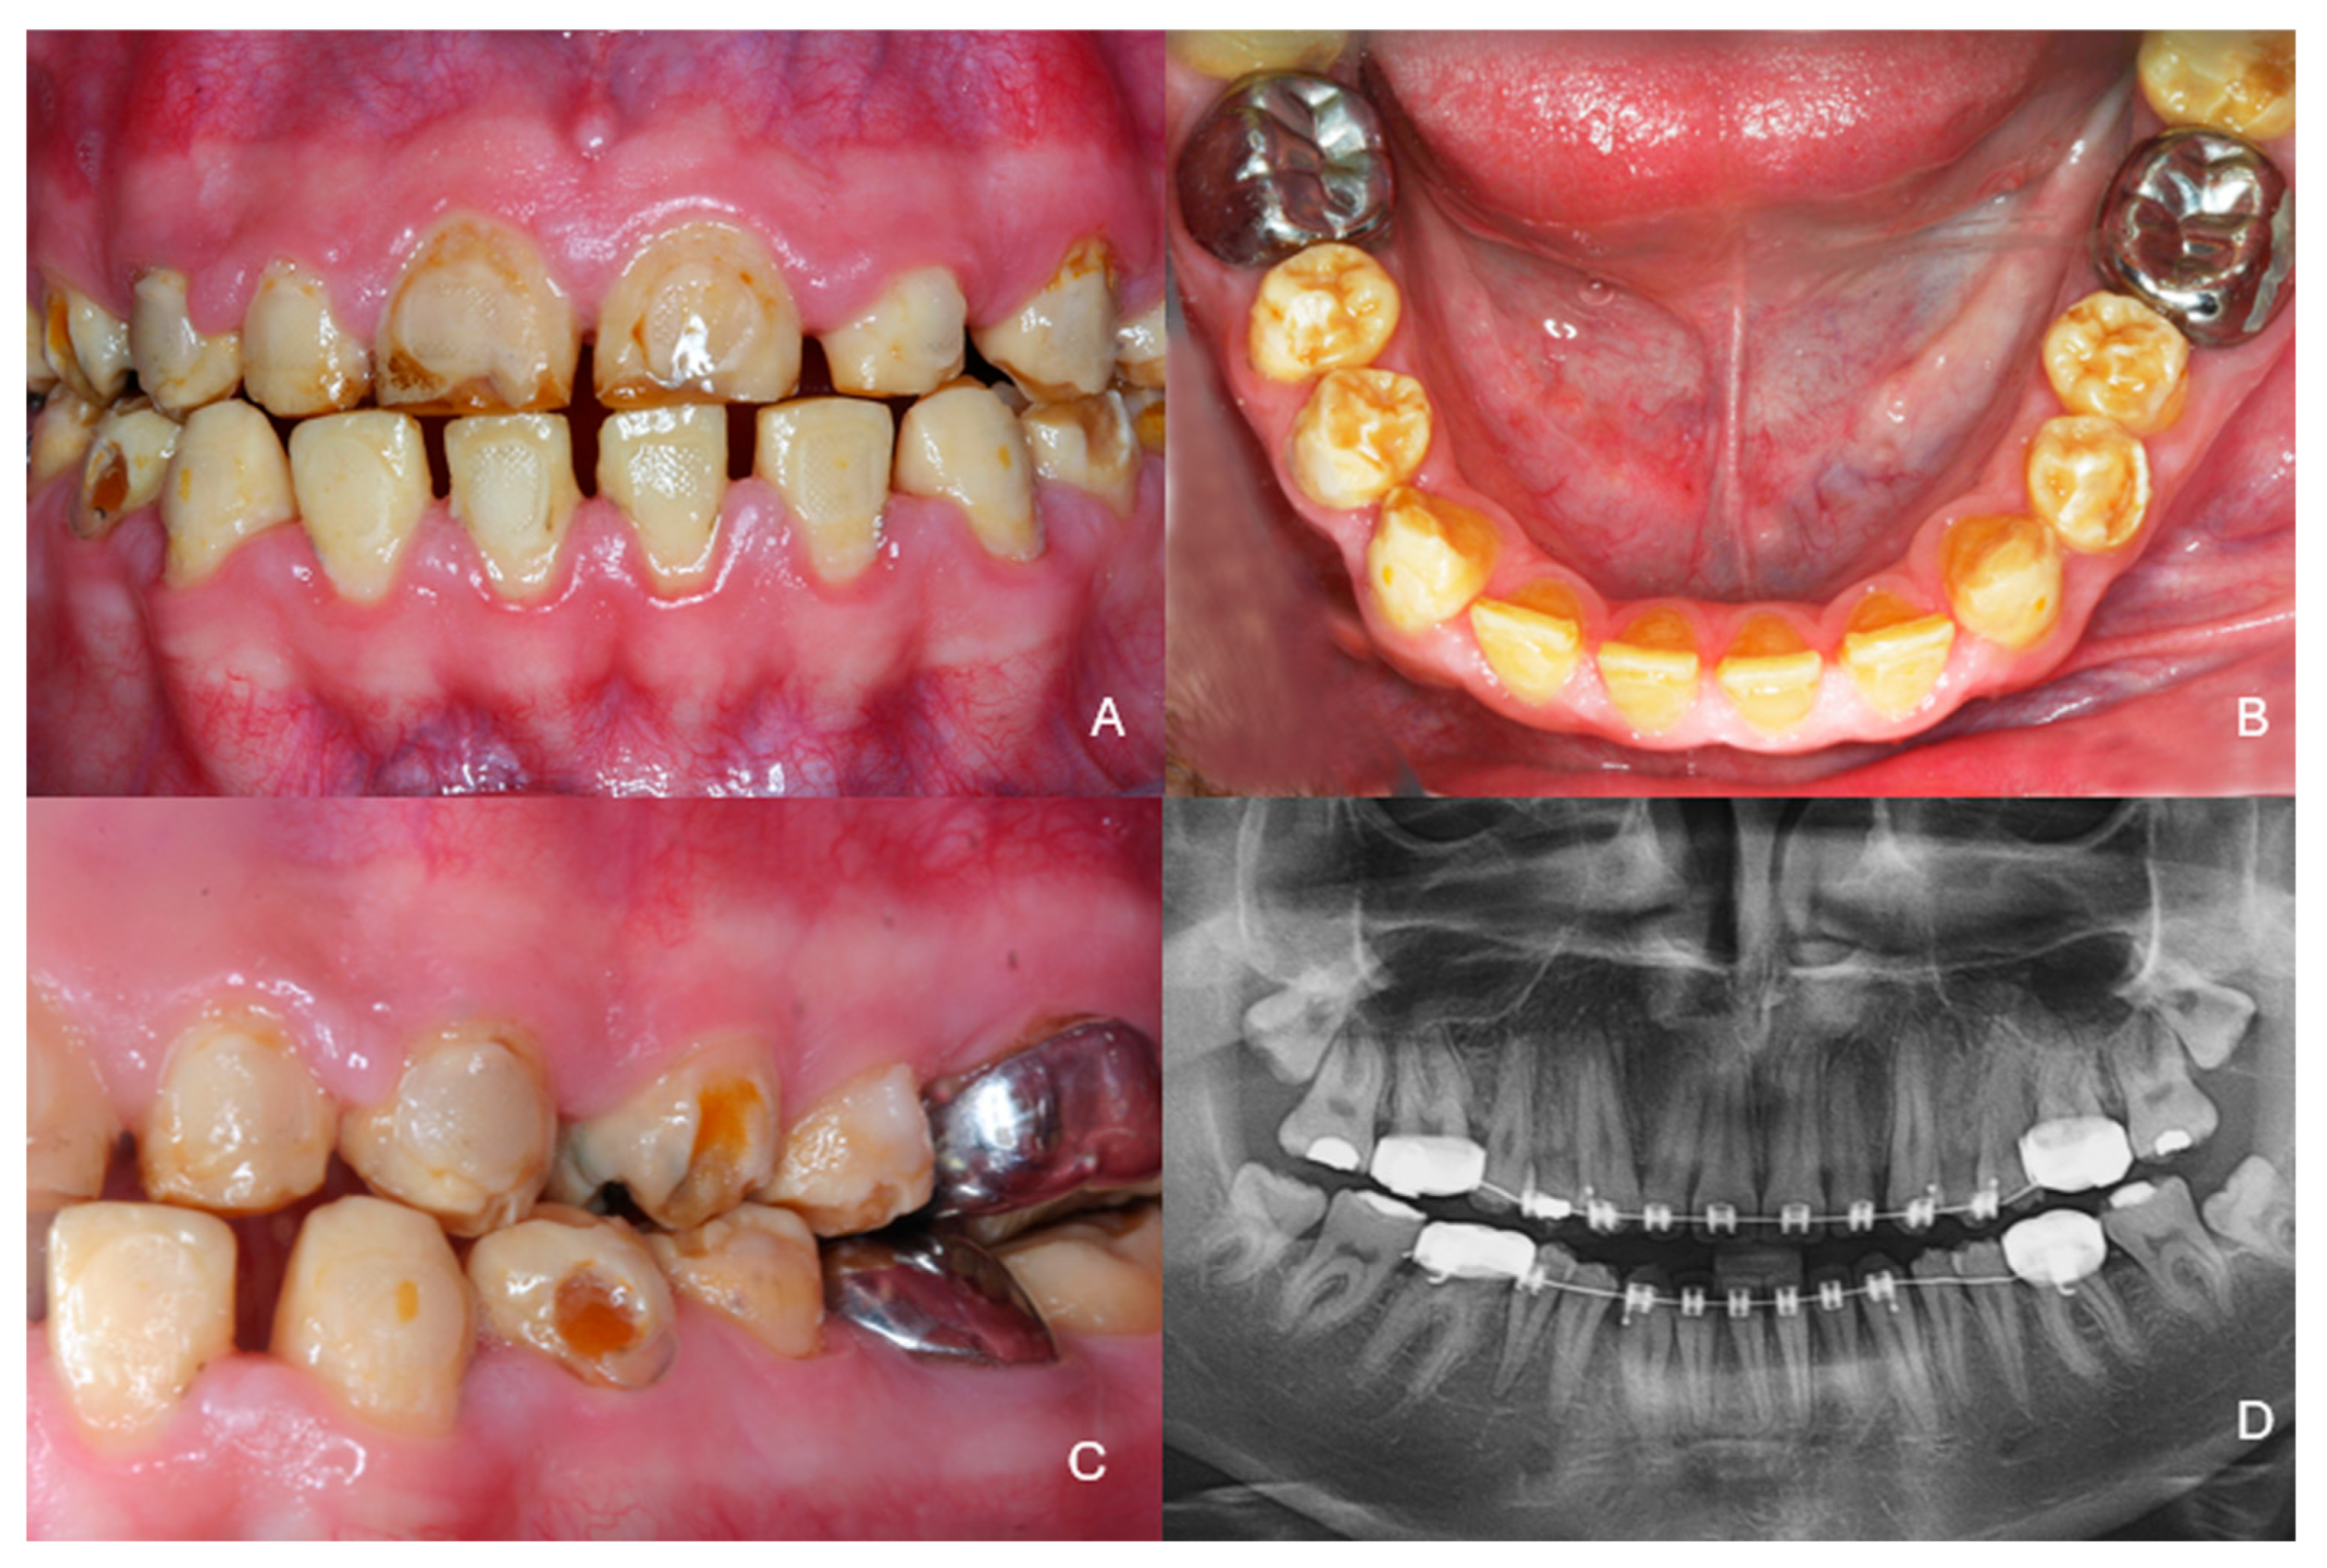

2. Case Presentation